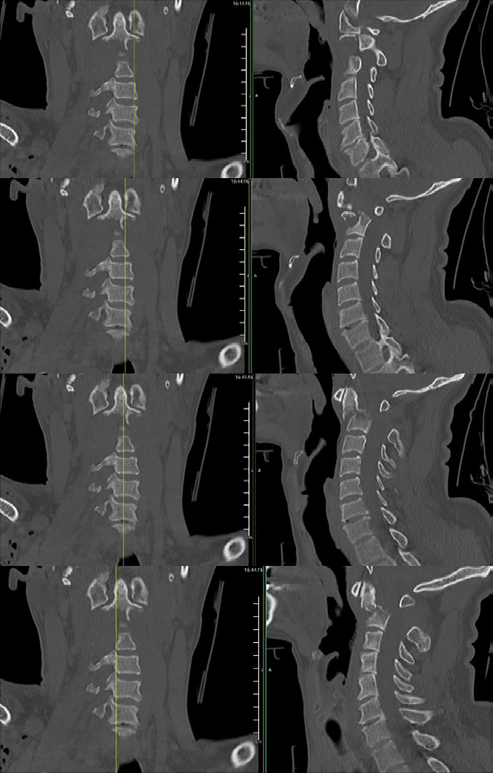

Se realiza TAC cervical donde se objetiva fractura inestable de apófisis odontoides de C2 tipo III de la clasificación de Anderson y D’Alonzo, con desplazamiento de 13,5 mm hacia posterior y disminución del canal raquídeo (tipo IIB según la clasificación de Roy-Camille).

Fractura inestable C2 con desplazamiento y compromiso del canal raquídeo.